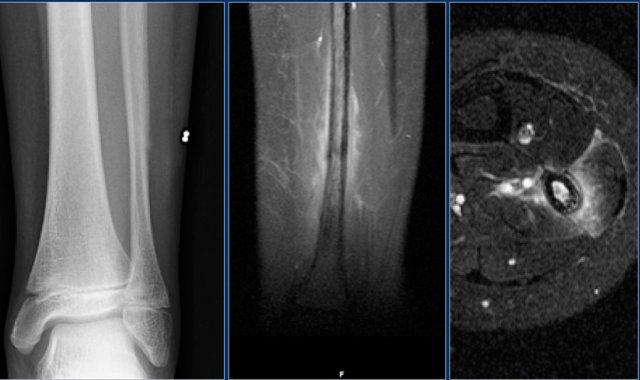

Đây là ví dụ về một bệnh nhân bị gãy xương do stress ở đầu xa xương mác.

Hình ảnh MR mặt phẳng coronal cho thấy đường giảm tín hiệu nhẹ đại diện cho đường gãy xương.

Chẩn đoán phân biệt dựa trên phản ứng màng xương và phù nề lan rộng:

- Osteomyelitis

- Eosinophilic granuloma